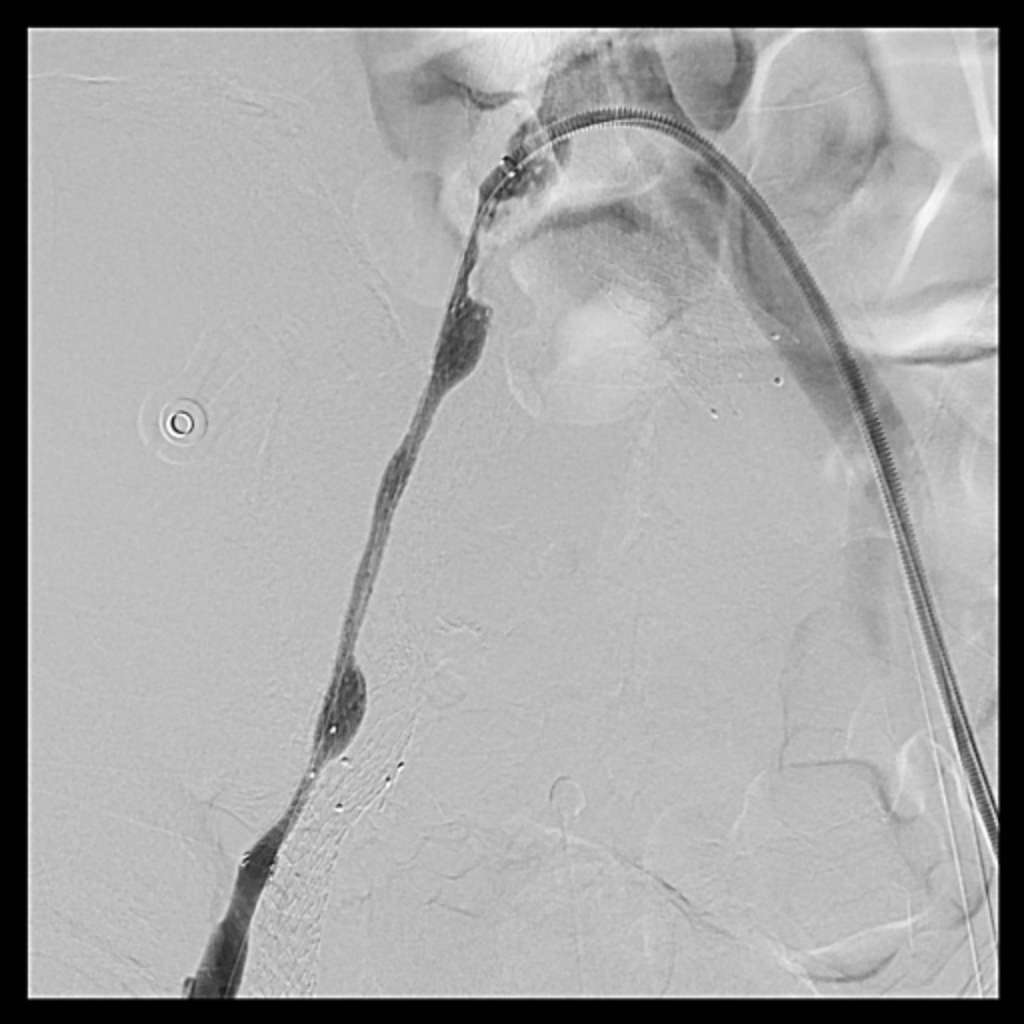

Venous access was obtained and venography confirmed heavy thrombus burden; therefore, the initial 6 Fr sheath was upsized to a 9 Fr sheath. Two Terumo stiff wires were advanced into the IVC to secure stable access. Mechanical thrombectomy using the Boston Scientific AngioJet system was performed from the right iliac vein to the right common femoral vein. During venography, unexpected early arterial opacification suggested an iatrogenic artery-to-vein fistula. Iliac angiography was then performed, revealing a total occlusion of the right common iliac artery with collateral reconstitution. To restore arterial flow and seal the fistula, a contralateral approach was used. A wire successfully crossed the occluded segment into the true lumen, followed by deployment of a covered stent. Final angiography showed complete closure of the fistula and restored antegrade arterial flow without distal embolization. The patient remained hemodynamically stable.